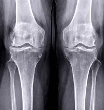

- X-ray, MRI 상 슬개대퇴 간격이 좁아져 있거나 연골 마모가 보이는 경우